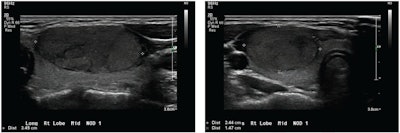

Thyroid nodules in children have traditionally been evaluated based on the overall impressions of radiologists looking at ultrasound images. The American College of Radiology (ACR) in 2017 developed a standardized TI-RADS risk-stratification system in order to decrease the number of unnecessary biopsies for benign nodules. The system aims to inform practitioners about which thyroid nodules require biopsy.

Yang and colleagues wanted to compare the impression of radiologists to TI-RADS, as well as a previously developed deep-learning algorithm in determining which thyroid nodules found on ultrasound are benign or malignant in children and young adults.